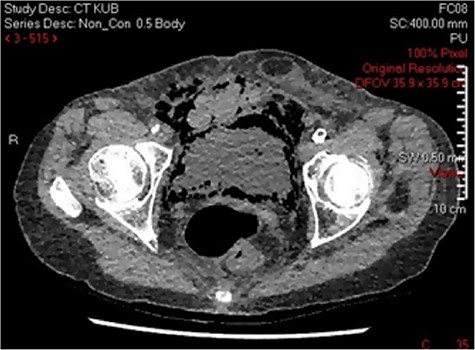

Three days post-procedure, the patient was confused and developed frank haematuria with a fall in haemoglobin from 124 to 107 g/L. A computed tomography (CT) scan of abdomen and pelvis demonstrated severe EC with abundant gas tracking outside of urinary bladder into the extraperitoneal space, extending to the anterior abdominal wall and inguinal orifice on the right, and obturator foramen on the left (Fig. 2). The urology on-call team recommended catheterization and treatment with empirical intravenous Piperacillin with Tazobactam for 5 days. A septic screen was undertaken including, blood tests and urine, wound, sputum and blood cultures. Klebsiella pneumoniae has cultivated in the urine culture, and subsequently, the microbiologist advised on converting drug regime to oral Trimethoprim based on culture sensitivities. The patient was discharged on the completion of the 14-day course of antibiotics.